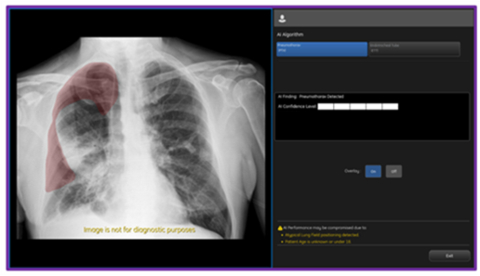

On-device, CCS2.1 output from GE HealthCare's AMX Navigate mobile X-ray system showing PTX overlay and confidence level. (Photo: GE HealthCare)

With this latest update, Critical Care Suite 2.1 provides immediate on-device detection and triage notifications for the presence or absence of pneumothorax (PTX). When a PTX is detected, an overlay is displayed in the area where the PTX was located both on-device as well as in PACS to assist with PTX localization, as well as improve speed and accuracy of PTX diagnosis. By hosting Critical Care Suite on-device, critical insights are available at the point of care and across the entire clinical care team.

Today GE HealthCare (Nasdaq: GEHC) announced an industry-first US FDA 510K clearance of Critical Care Suite 2.1 featuring a Pneumothorax (PTX) algorithm for the detection, notification, triage and diagnosis of PTX. The updated PTX algorithm expands Critical Care Suite’s on-device triage capabilities by providing immediate notification of the presence or absence of pneumothorax, as well as an overlay display both on-device and in PACS to assist with PTX localization.